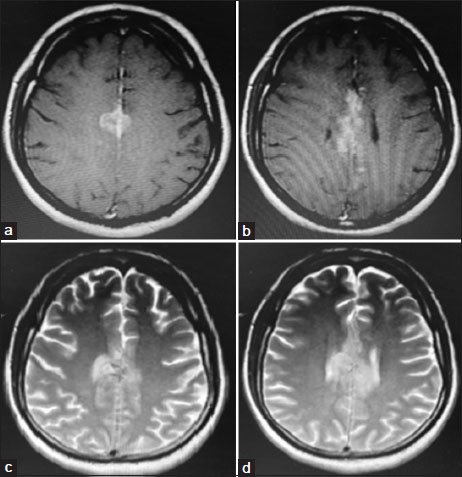

On evaluation, magnetic resonance imaging brain and thoraco-lumbo-sacral spine showed heterogeneous hyperintense lesion [Figure 1] in the parasagittal region and patchy dural enhancement in the cervicodorsal region. Videostroboscopy showed left vocal cord palsy. Fluorodeoxyglucose PET-CT ruled out disease at other sites. These findings pointed to bulbar palsy as a possible cause of his hoarseness of voice and dysphagia. The bulbar palsy was likely a result of leptomeningeal disease. CSF was planned to confirm the same. CSF showed atypical cells, which were suspicious of malignancy, CSF protein was 266.7 mg/dl, and glucose was 29.4 mg/dl. To confirm the diagnosis and primary, IHC markers were done on cell blocks from CSF [Figure 2]. Cell block from CSF showed malignant cell clusters in [Figure 2]a and [Figure 2]b. CK7-positive cells are in [Figure 2]c and MUC-1 (Mucin-1, cell surface associated protein (clone MMAB,BioSB))-positive cells in [Figure 2]d. Cells were negative for CK20 and CDX2. Diagnosis of metastatic adenocarcinoma was confirmed on CSF with strong MUC1 staining favoring pancreatobiliary origin. For dysphagia, nasogastric feeding was started. Intrathecal chemotherapy (IT) was given with methotrexate and hydrocortisone weekly. Post 3 weeks of IT chemotherapy, the patient had symptomatically improved. However, the patient succumbed to chest infection in April 2020.

| Figure. 1(a and b) T1-weighted images showing intermediate signal lesions. (c and d) T2-weighted images showing hyperintense lesions

| Figure. 1(a and b) T1-weighted images showing intermediate signal lesions. (c and d) T2-weighted images showing hyperintense lesions